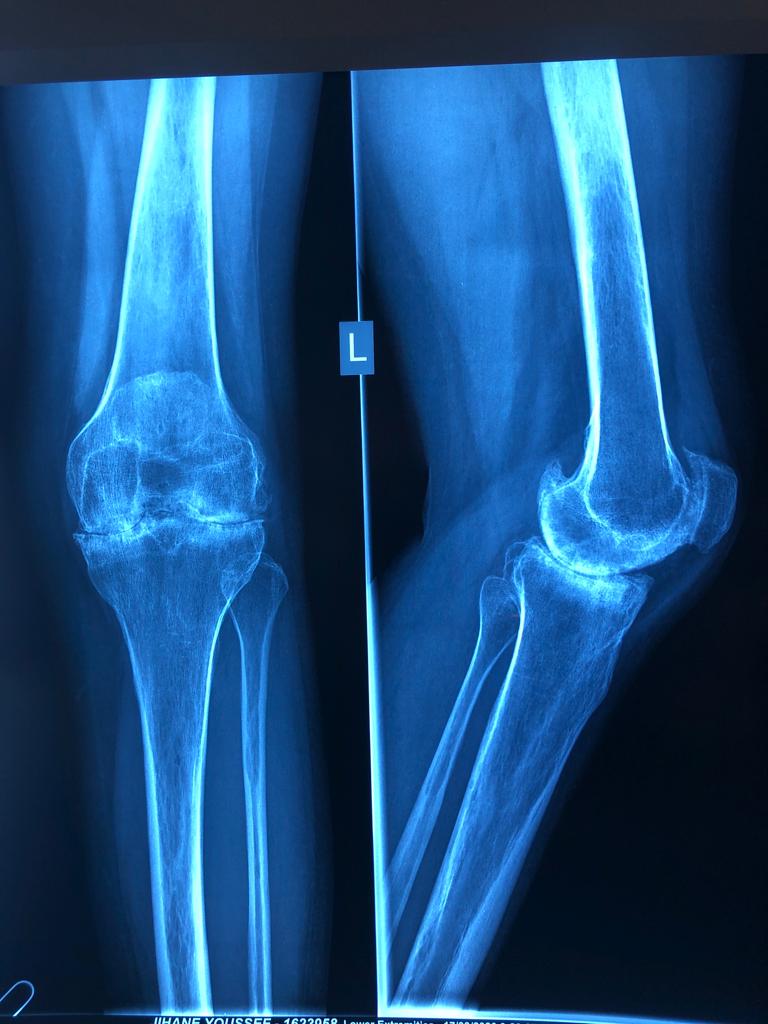

Total Knee Replacement